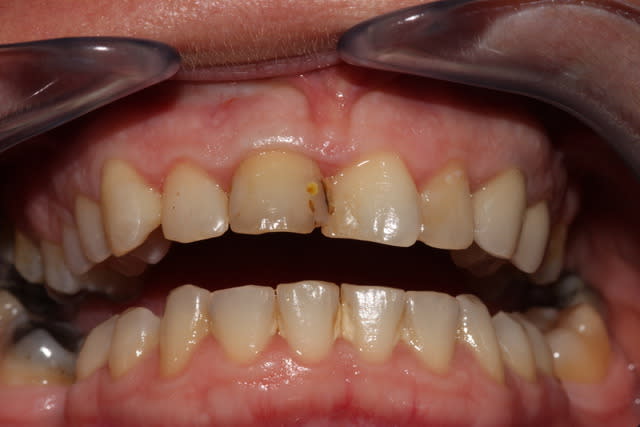

Je stressais pas mal sur ce cas quant à la réussite du conj. enf. avec lamb. tracté coronairement. Mais le résultat est acceptable je pense, car on partait de loin.